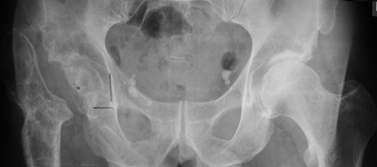

[Ortho] Клинический разбор пациентки с ложным суставом шейки правой бедренной кости

Имя     : 1.12.13small.JPG

Url     : http://weborto.net:8080/pipermail/ortho/attachments/20160219/e0faf22a/attachment-0002.jpeg